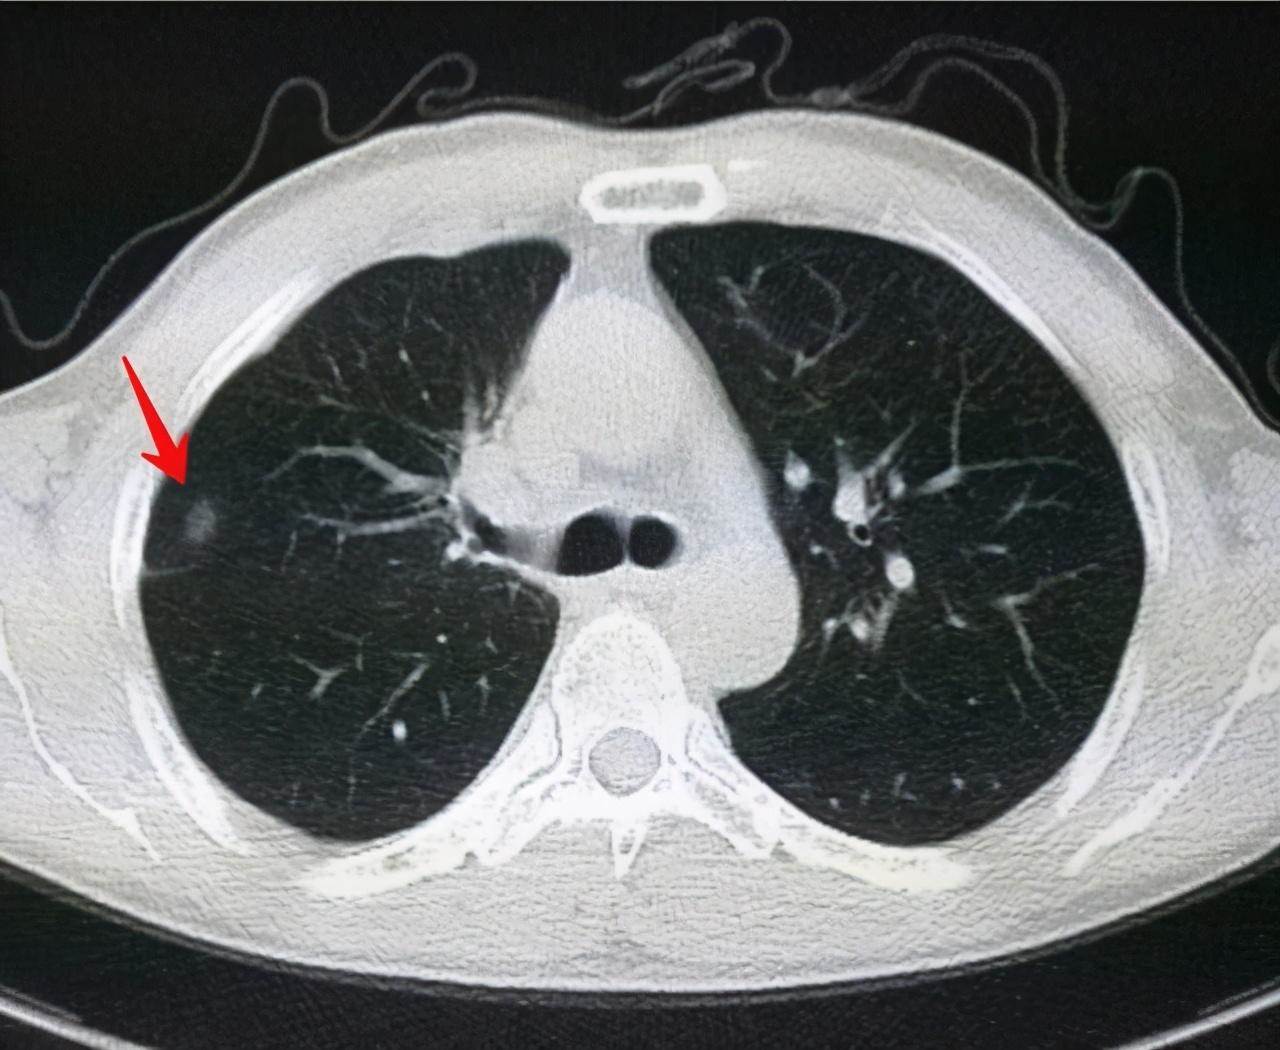

肺结节并非某种疾病的名称,而是一个影像学术语,即正常的肺组织内多出了一些较小的、局限的、椭圆形或不规则形状的生理或病理性组织,在CT或胸片上就显示出类似结节的形态。查出肺结节不需要太紧张,因为肺结节不等于肺癌。肺结节不罕见,湘雅医院早期肺癌筛查项目数据显示,30-70岁人群中检出率超出70%,但最后病理确诊的肺癌患者仅为筛查总人数的1%~2%,90%的肺结节是良性的。

那么,如果体检CT查出的肺结节,我们如何判断它会不会是肺癌呢?其实我们可以根据肺部结节的直径范围来判断其性质并采取针对性措施。

如果患者的肺部结节直径在7-10毫米范围内,并呈现玻璃样结节状,临床医师建议该类患者先保持三个月左右的密切观察。可以借助于CT影像对于病情进行进一步的分类,一般可分为纯磨玻璃结节、混合性磨玻璃结节以及实性结节。而在这三种肺部结节当中,属于实性结节患者的恶化几率较高。建议这患者保持对于自身病情的密切观察,在三个月之后视病情发展来决定是否进行手术。